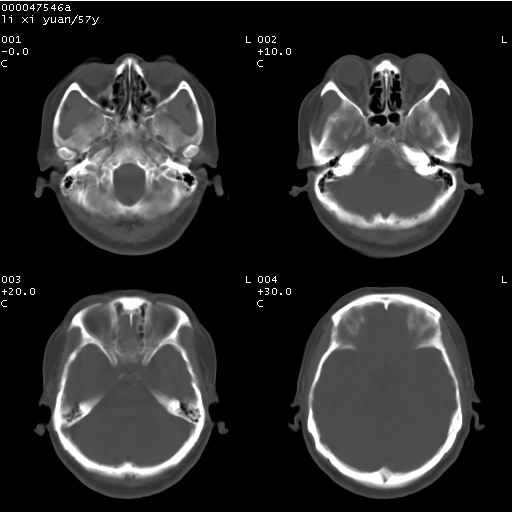

以下是引用余辉在2008-4-27 14:02:00的发言:[br]病灶位于中央沟前方?位于额叶?高密度灶,灶周水肿不明显,病灶似沿脑沟走行,强化明显,局部层面呈现环状强化,考虑1脑表面血管性疾病,如血管瘤,血管扩张,灶内血栓形成,其次考虑肿瘤如脑膜瘤、转移瘤,胶母等

以下是引用形影不离在2008-4-27 14:13:00的发言:[br]考虑胶质瘤可能性大,不排除慢性炎性肉芽肿。建议mri检查。